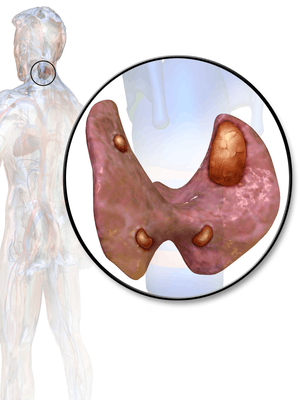

Hyperparathyroidism is an increased parathyroid hormone (PTH) levels in the blood.[1] This occurs either from the parathyroid glands inappropriately making too much PTH (primary hyperparathyroidism) or other events triggering increased production by the parathyroid glands (secondary hyperparathyroidism).[2] Most people with primary disease have no symptoms at the time of diagnosis.[3] In those with symptoms the most common is kidney stones with other potential symptoms including weakness, depression, bone pains, confusion, and increased urination.[2][4] Both types increase the risk of weak bones.[4][3]

Primary hyperparathyroidism in 80% of cases is due to a single benign tumor known as a parathyroid adenoma with most of the rest of the cases due to a multiple benign tumors.[4][2] Rarely it may be due to parathyroid cancer.[4] Secondary hyperparathyroidism typically occurs due to vitamin D deficiency, chronic kidney disease, or other causes of low blood calcium.[2] Diagnosis of primary disease is by finding a high blood calcium and high PTH levels.[4]

In primary hyperparathyroidism about 75% of people have no symptoms.[2] The problem is often picked up during blood work for other reasons via a raised calcium.[3] Many other people only have non-specific symptoms. Symptoms directly due to hypercalcemia are relatively rare, being more common in patients with malignant hypercalcemia. If present, common manifestations of hypercalcemia include weakness and fatigue, depression, bone pain, muscle soreness (myalgias), decreased appetite, feelings of nausea and vomiting, constipation, polyuria, polydipsia, cognitive impairment, kidney stones (See Foot Note[nb 1]) and osteoporosis.[9] A history of acquired racquet nails (brachyonychia) may be indicative of bone resorption.[10] Parathyroid adenomas are very rarely detectable on clinical examination. Surgical removal of a parathyroid tumor eliminates the symptoms in most patients.

Primary hyperparathyroidism results from a hyperfunction of the parathyroid glands themselves. There is oversecretion of PTH due to a parathyroid adenoma, parathyroid hyperplasia or, rarely, a parathyroid carcinoma. This disease is often characterized by the quartet stones, bones, groans, and psychiatric overtones referring to the presence of kidney stones, hypercalcemia, constipation and peptic ulcers, as well as depression, respectively.[13][14]